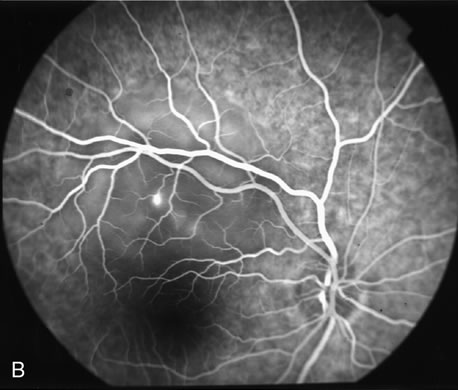

The differentiation of a partial-thickness, or lamellar, macular hole from a full-thickness macular hole can be challenging, and FA is often helpful in assisting in the diagnosis.55 As in a full-thickness hole, a lamellar hole presents as an excavation of the retina, and the presence of drusen underneath the lamellar hole can simulate the yellow deposits seen at the base of full-thickness holes. Occasionally, there is a full-thickness hole at one side of a lesion, and the rest of the lesion consists of a lamellar defect. FA will show immediate hyperfluorescence from the choroidal circulation under a full-thickness hole (Fig. 34A), whereas a lamellar hole, with a relatively intact RPE, will block some of the normal fluorescence from the choriocapillaris (Fig. 34B).

Fig. 34. Full-thickness and partial macular holes. A. There is a discrete hole in the central macula. Hyperfluorescence reflects choriocapillaris leakage that is normally partially blocked by retinal pigment epithelium. B. There is partial blockage of the choroidal hyperfluorescence, but subtle hyperfluorescence is visible. (Courtesy of Dr. Peter Judson.)